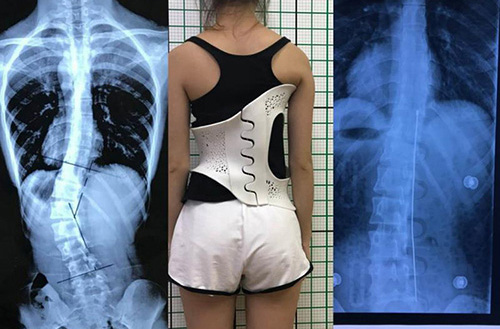

此外,在外固定支具研制方面,3D打印所起到的作用也不容忽視。對(duì)于意外摔傷導(dǎo)致骨折的患者來(lái)說(shuō),適宜的熱塑夾板、可卸式泡沫夾板、高分子夾板等外固定支具,有助于幫助患者快速恢復(fù),并降低發(fā)生二次骨折的風(fēng)險(xiǎn)。

3D打印技術(shù)在骨科的實(shí)際應(yīng)用有哪些?(圖4)

(3D掃描和3D打印技術(shù)輔助制造的個(gè)性化脊柱矯正支具)